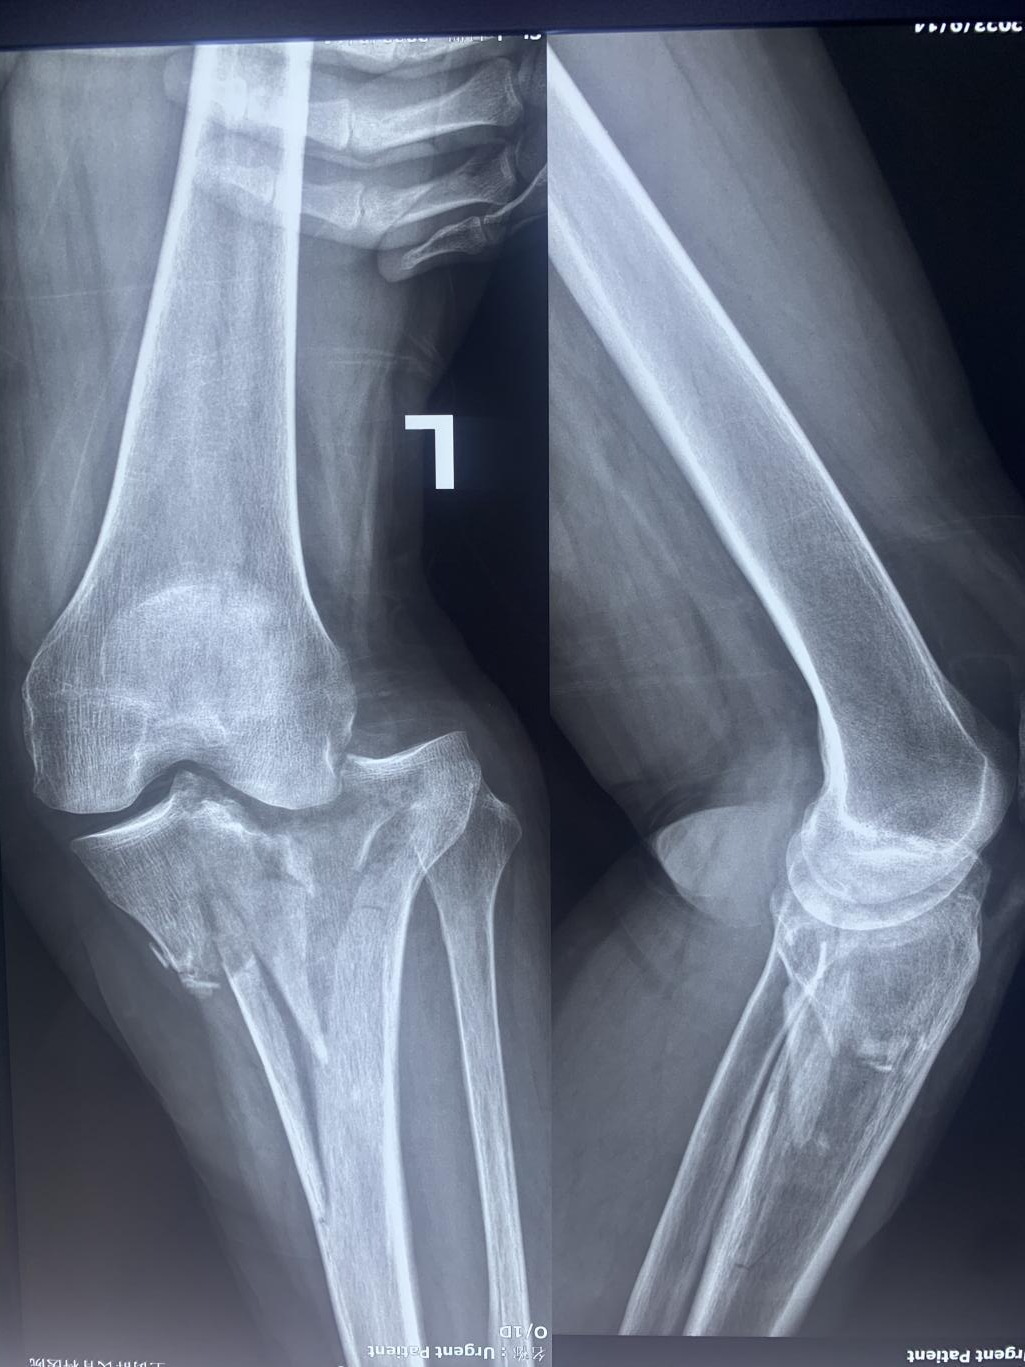

Patient-Wang Yanping, female, 60 years old.She was admitted to the hospital on 14 September 2023 with the chief complaint of "pain and limited movement of the left knee joint for 2 hours after a fall. She was then sent by her family to Zhengzhou Orthopaedics Hospital for treatment.

X-ray upon admission